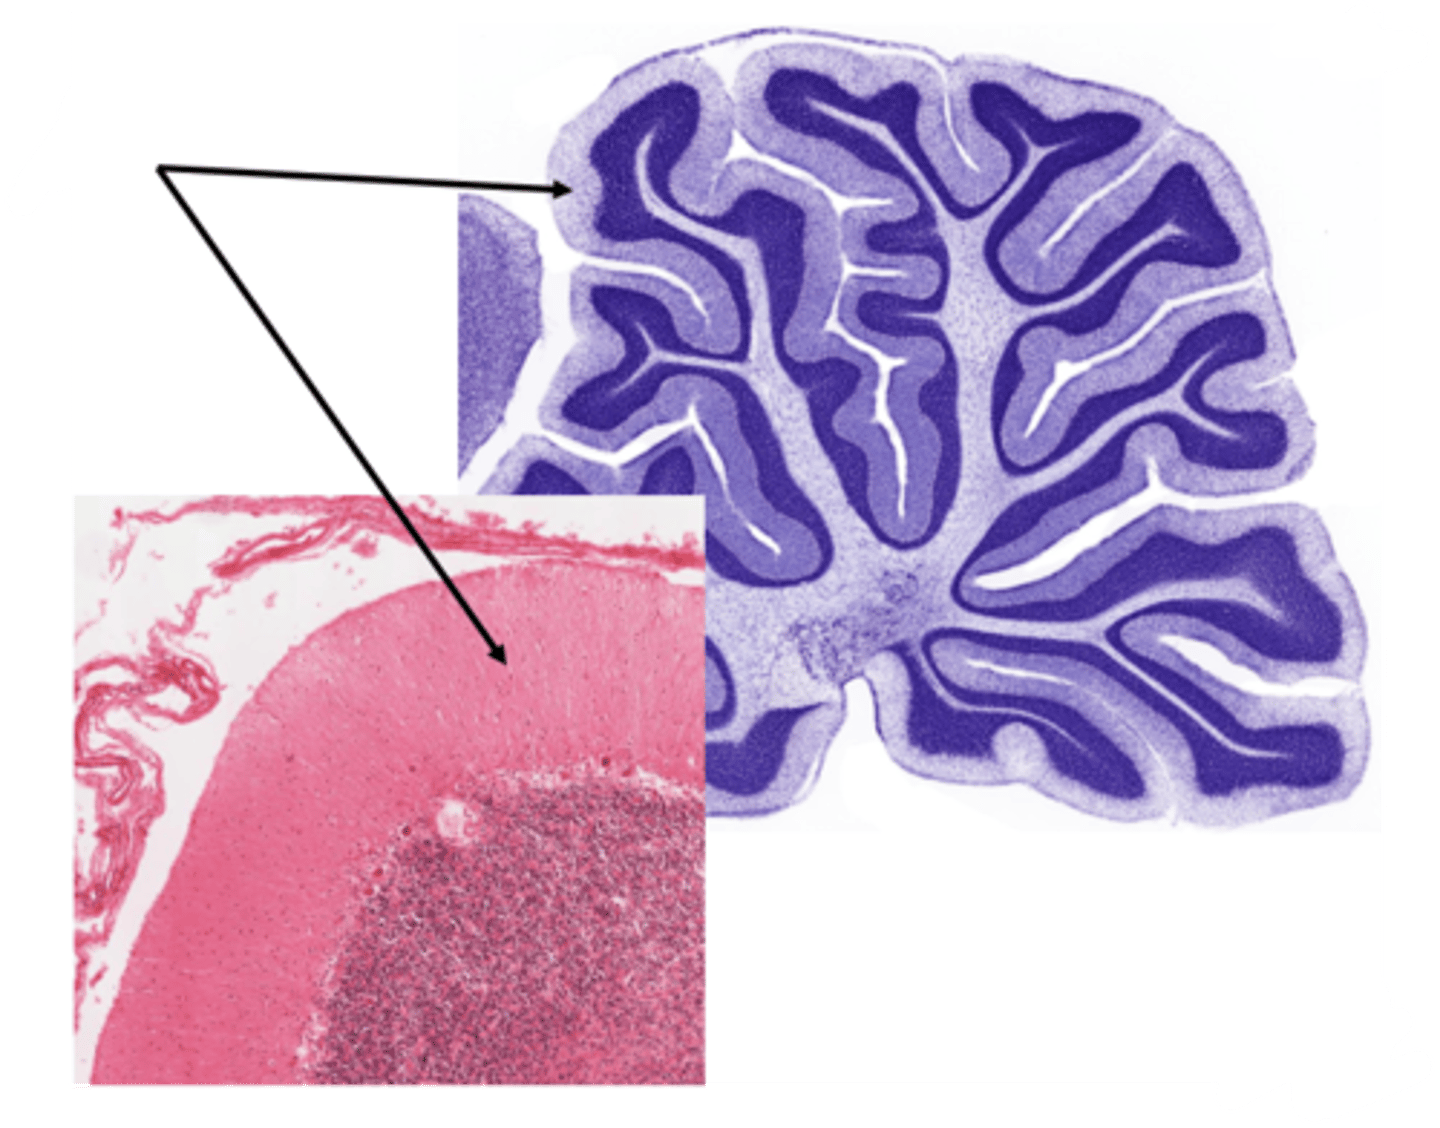

Identify the portion of the CNS

cerebellum

Identify the layer of the cerebellum

molecular layer

white matter

purkinje layer

pia mater

granular layer